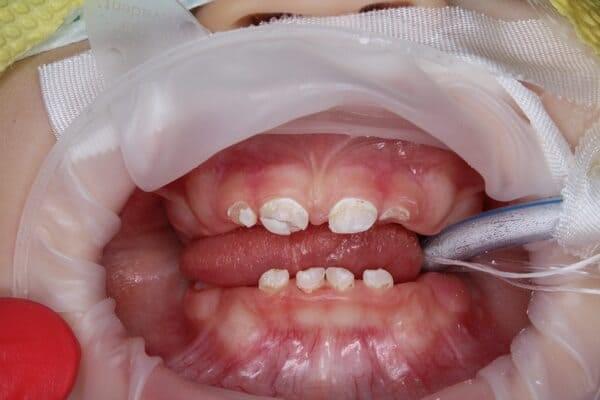

Пацієнт 2 років, уражено десять зубів, шість із яких потребують покриття коронками. В зв’язку зі значним об’ємом та складністю лікування прийнято рішення про лікування в умовах анестезіологічного забезпечення. Раніше була спроба пролікувати ці зуби застарілими методами, які не тільки не є ефективними відносно лікування, а ще і додають дитині комплексів через характерне фарбування зубів. Через високи естетичні вимоги дитини і батьків було прийнято рішення покривати естетичними цирконієвими коронками, як передні так і бічні зуби. Через 2,5 години дитина без інфекції в порожнині рота, з відновленим здоров’ям та естетикою посмішки може кусати, жувати, посміхатись без болю та дискомфорту. Останнє фото через 2 роки після лікування, оскільки естетичні коронки в дитячій стоматології - це надійність, естетика та функція.